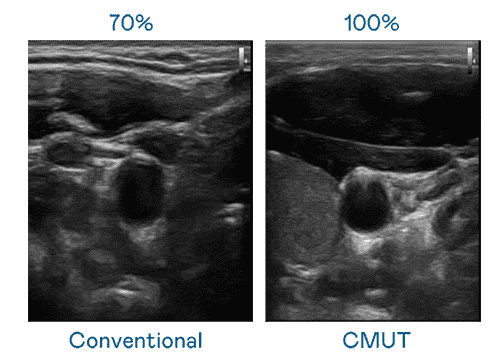

CMUT 技术是一种用电容式微机电元件来产生超音波讯号的技术。。。。与传统 PZT 压电式技术相比,,,,CMUT 频宽增加 30%,,,更宽频的超音波讯号让影像解析度大幅提升,,,是实现高影像品质医疗超音波扫描、、促进精准医疗发展的关键技术。。。。

大频宽带来超清晰影像

超音波影像的解析度高低,,,,首先取决于探头能发出的讯号频宽。。。。PG国际 CMUT 可提供高清晰的超音波讯号,,,提供高频宽、、、高灵敏度、、、、影像纹理细节更高的超音波影像,,,,协助医护人员缩短影像判读时间及利用精准的医疗影像进行诊断。。。。